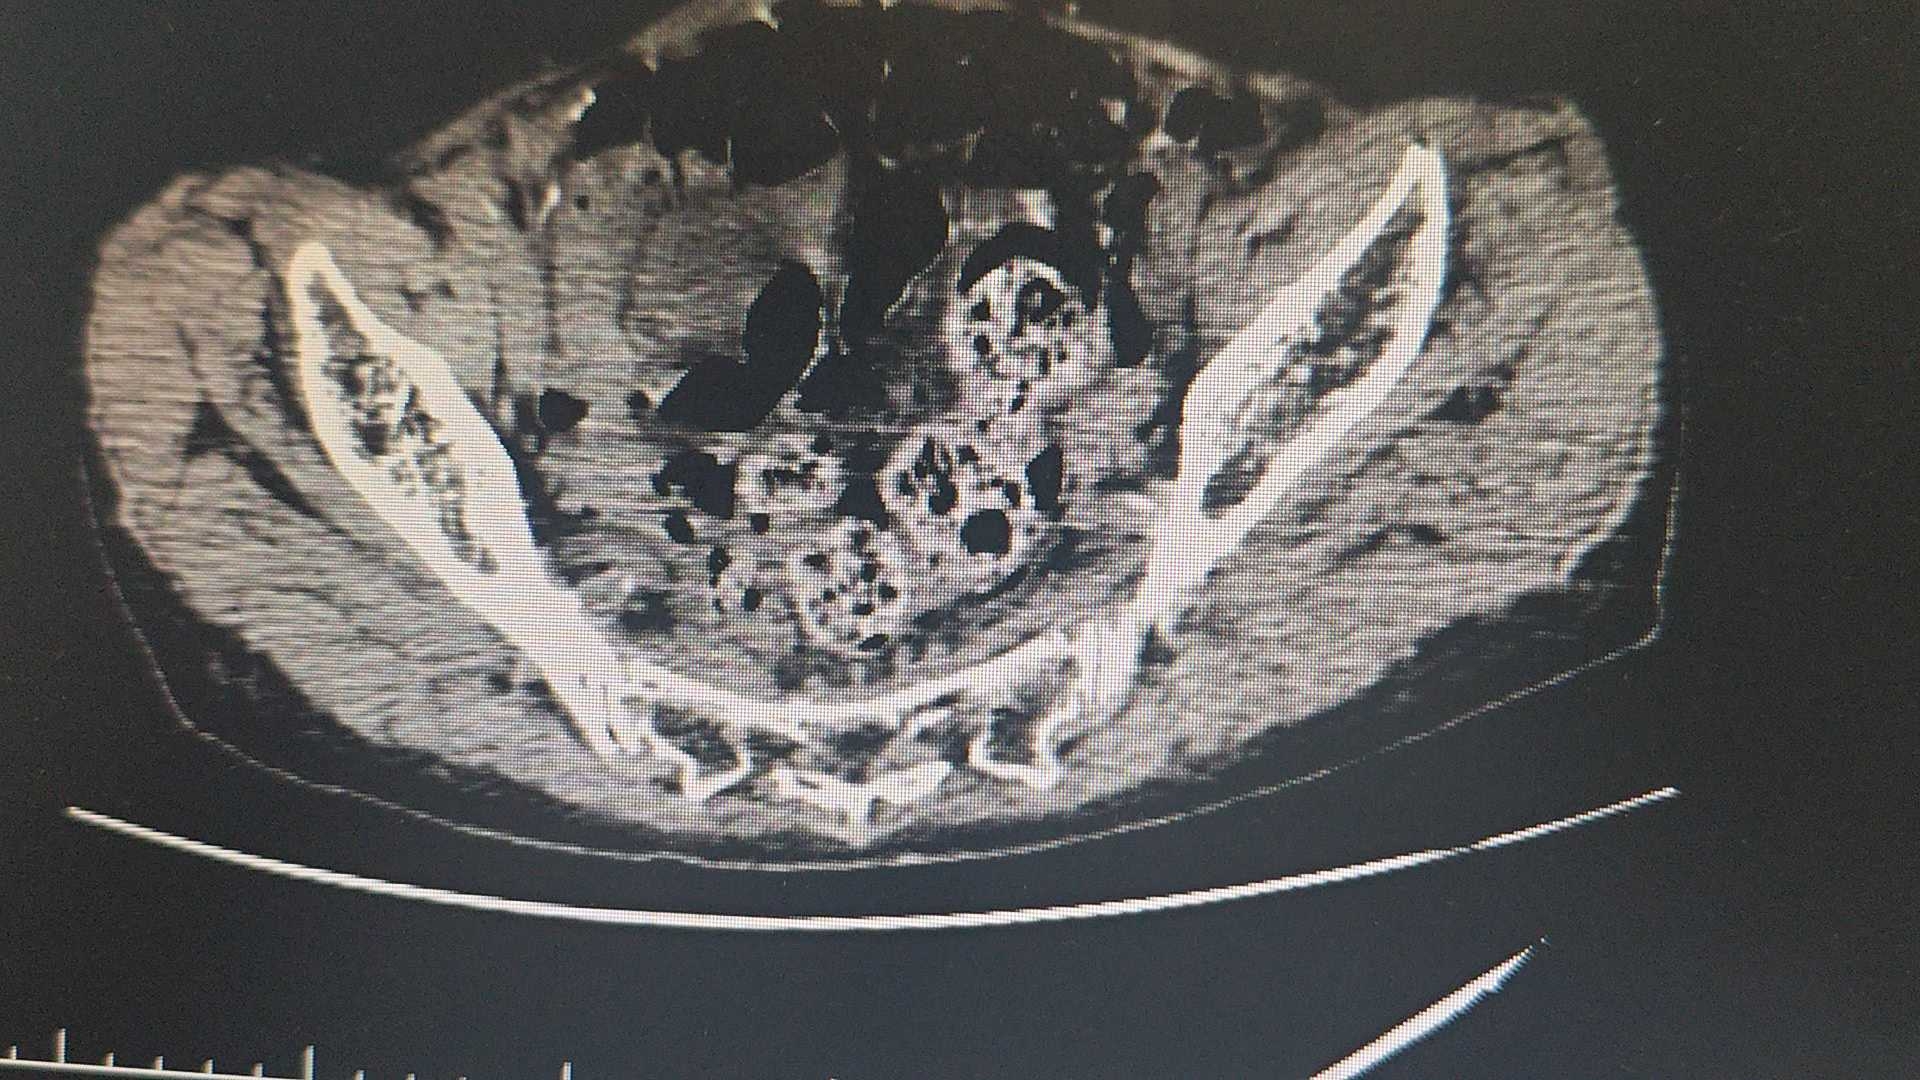

70岁女性,周身乏力半月入院。

请教一下,这子宫是不是有点奇怪。